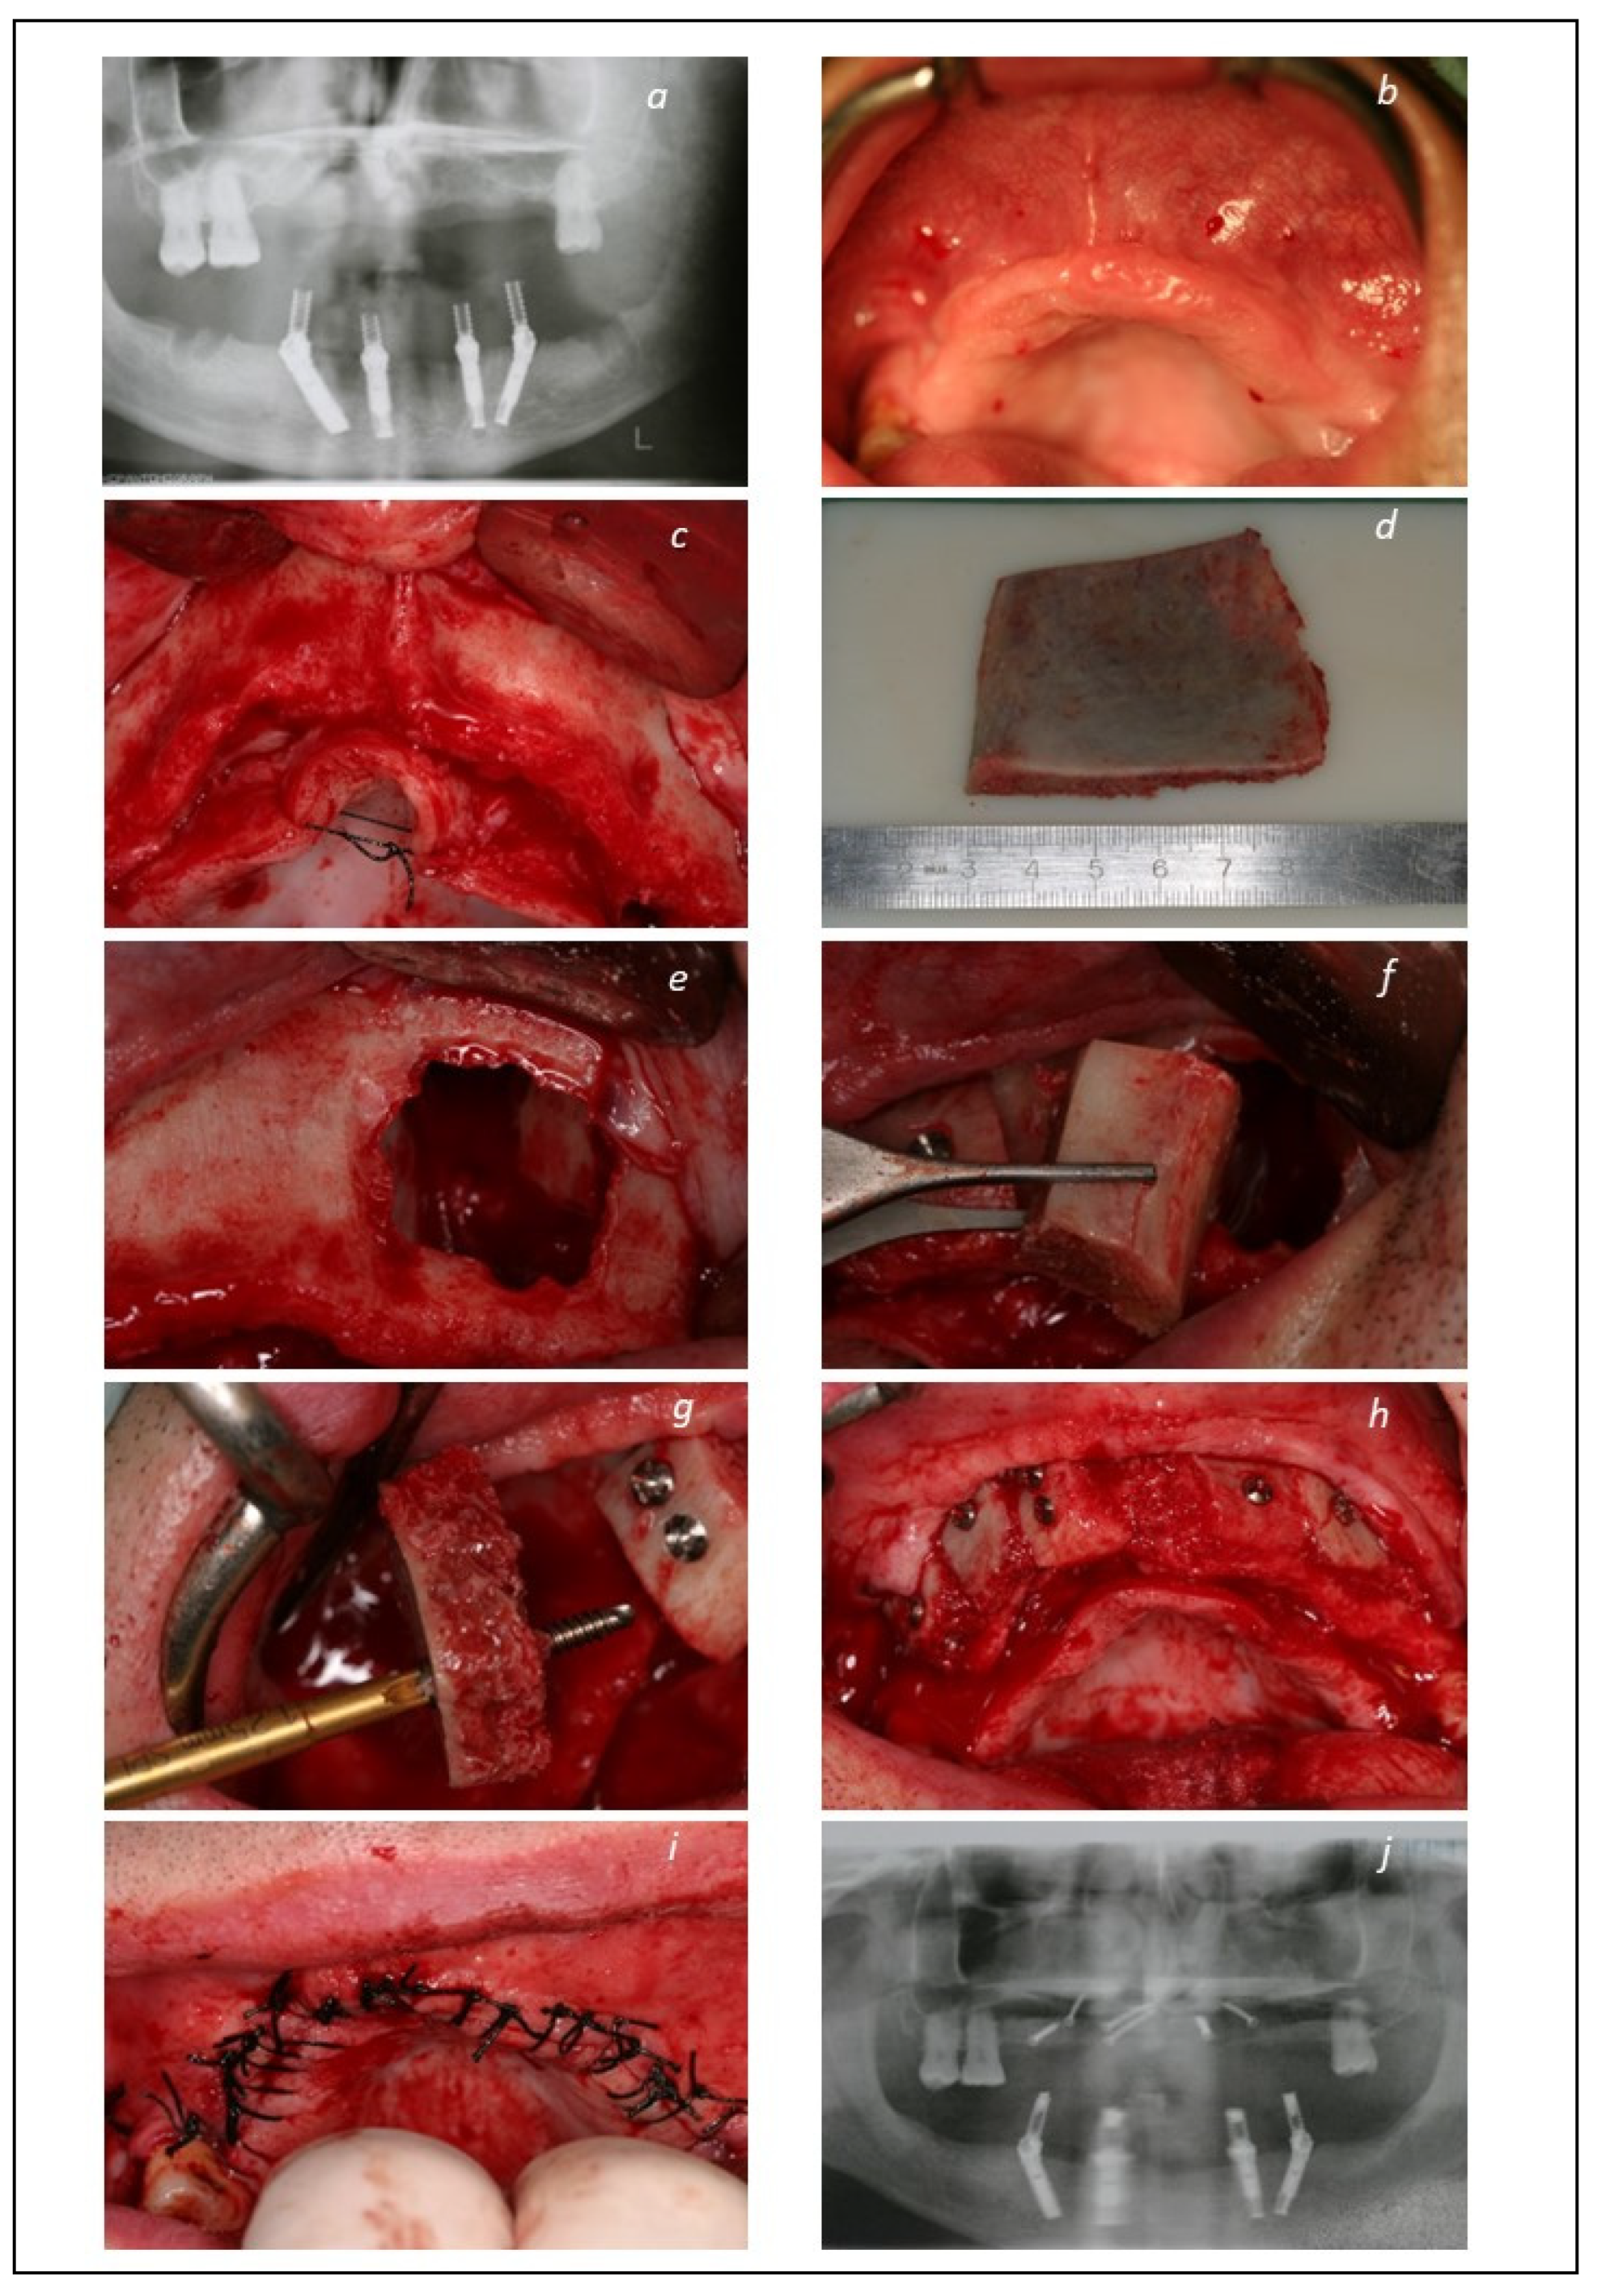

2.2. Surgical and Prosthetic Protocols